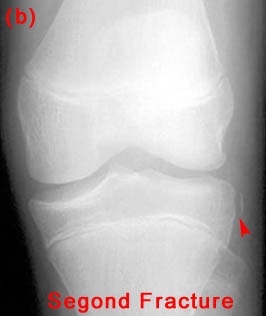

27) A patient is known to have a torn ACL and presents for x-ray examination of the knee. Which of the following abnormalities is often associated with a torn ACL?

"B&C" - Both Segond fractures and tibial plateau fractures are commonly associated with ACL tears.

28) Name the abnormality shown in the image below.

29) Give the specific name for the fracture type shown in the image above. Avulsion